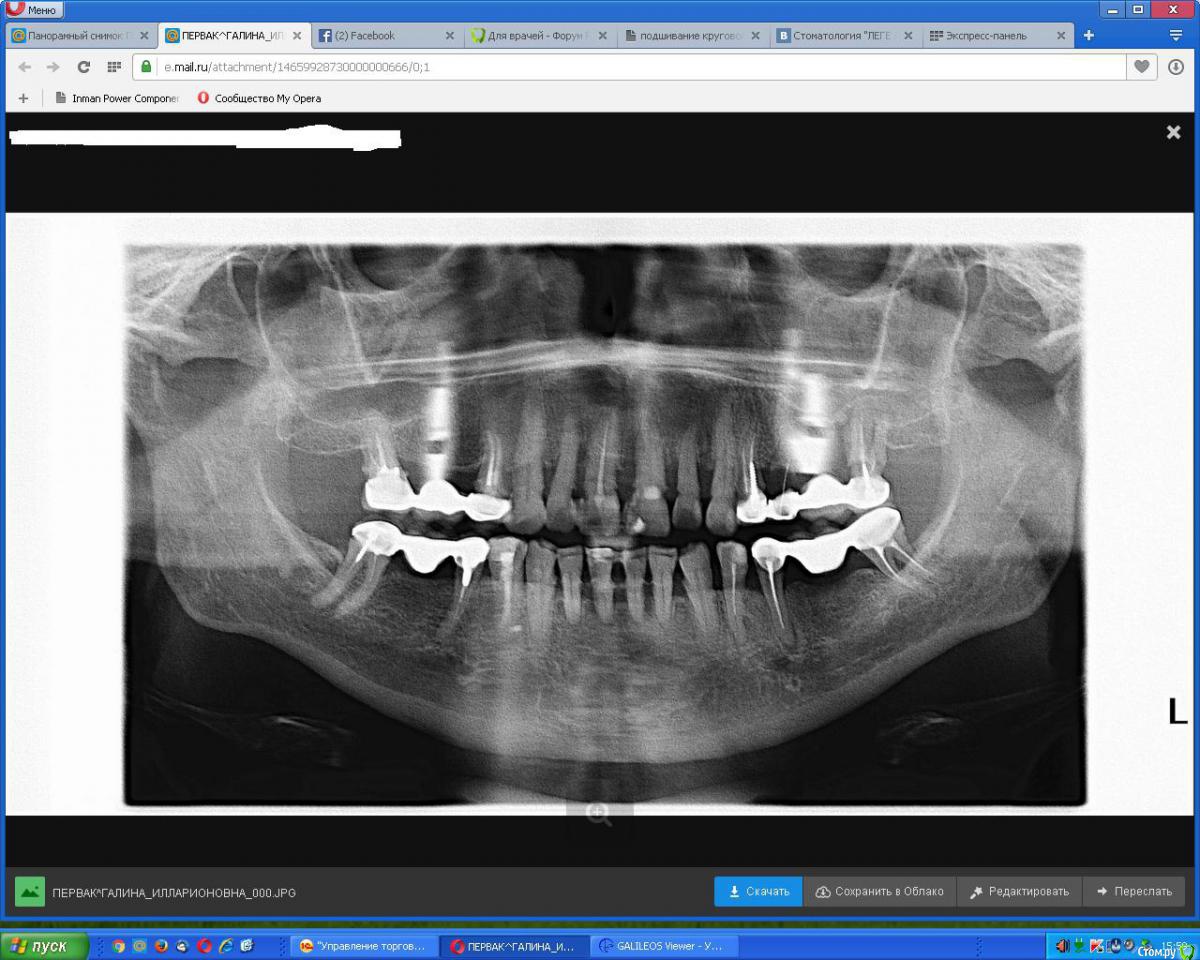

an_ver Опубликовано 15 июня, 2016 Поделиться Опубликовано 15 июня, 2016 При панорамном на в\ч в обл.16,26...что это? Импланты? Почему нет соединения абатмент-имплант? Ссылка на комментарий

Чертков Александр Опубликовано 15 июня, 2016 Поделиться Опубликовано 15 июня, 2016 Андрей, по моему это артефакт 2 Ссылка на комментарий

AlexanderGudkov Опубликовано 15 июня, 2016 Поделиться Опубликовано 15 июня, 2016 (изменено) +1, иногдаа так серьги отсвечивают Изменено 15 июня, 2016 пользователем AlexanderGudkov 2 Ссылка на комментарий

Jurai Опубликовано 15 июня, 2016 Поделиться Опубликовано 15 июня, 2016 Серьги не сняли) 1 Ссылка на комментарий

Nazim_NV86 Опубликовано 15 июня, 2016 Поделиться Опубликовано 15 июня, 2016 Серьги-имланты. Ссылка на комментарий

Доктор Добрых Дел Опубликовано 15 июня, 2016 Поделиться Опубликовано 15 июня, 2016 Серьги однозначно Ссылка на комментарий